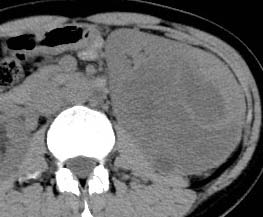

But, when we analyzed the degree of enhancement (hyperdensity, isodensity, hypodensity) in arterial (corticomedullary) and venous (nephrographic) phases showed significant difference. In arterial phase, most of clear cell RCC (21 of 39, 53.8%) showed hyperdensity, whereas none of non -ccRCC (0 of 22,0%) showed hyperdensity. The P value was 0 (P<0.05). In venous phase, ccRCC showed more hyperdensity or isodensity (9 and 4 0f 39, 23.1% and 10.3% respectively) than non-ccRCC (0 and 1 of 22, 0% and 4.5% respectively). Almost all of the non-clear cell RCC ( 21 However, we did not get any significant difference, when compared degree of enhancement in delayed phase (excretory phase). Table 3: shows the comparison of degree of enhancement in different phases in between ccRCC and non-ccRCC. The pattern of enhancement (homogeneous or heterogeneous) showed significant difference. Nonclear cell carcinoma (19 of 22, 86%) showed more heterogeneous enhancement pattern than that of clear cell carcinoma (21 of 39,53%). The P value was 0.012 (p<0.05).

Now-a-days, the incidence of renal cell carcinoma is increasing due to increasing risk factors (obesity, smoking) and utilization of modern imaging techniques [11][12][13]29]. A majority of renal tumors are incidentally diagnosed on medical imaging, that's why most of them are asymptomatic, small in size and present at an earlier stage [14,27]. It is important to discriminate clear cell RCC from non-clear cell RCC because of ccRCC is generally considered to have a worse prognosis and is treated differently than other subtypes [15][16][17][18]27]. Several study has been done previously to differentiate clear cell RCC from non-clear cell RCC by using imaging modalities. The most consistent finding was that, degree of enhancement was the most valuable parameter for differentiation of renal cell carcinoma subtypes. Clear cell RCC S enhance to a greater degree than other subtypes of malignant lesions [8,10,[19][20][21][22]. Some researchers stated that the strong enhancement of conventional renal carcinoma is caused by it , s rich vascularity and alveolar architecture at histologic examination [4,10,23]. Our study consistent with these study. In this study, we found ccRCC (53.8%) showed more hyperdensity than that of non-ccRCC(0%). Most of non-ccRCC (95.5%) had hypodensity in all phases.

However, when we compared pattern of enhancement, most of clear cell RCC (53.5%) showed heterogeneity, which agree with other studies related with pattern of enhancement of ccRCC [8,10]. But, when we made comparison of heterogeneity in between ccRCC and non-ccRCC, we found that, non-ccRCC were more heterogeneous than ccRCC. This may be because of larger size of non-ccRCC S which tended to show heterogeneity due to propensity of hemorrhage, necrosis and calcification [24][25][26]. At microscopic examination, all tumors with homogeneous enhancement were mainly composed of solid elements, whereas all tumors with heterogeneous enhancement had solid elements, necrosis, hemorrhage and calcifications.